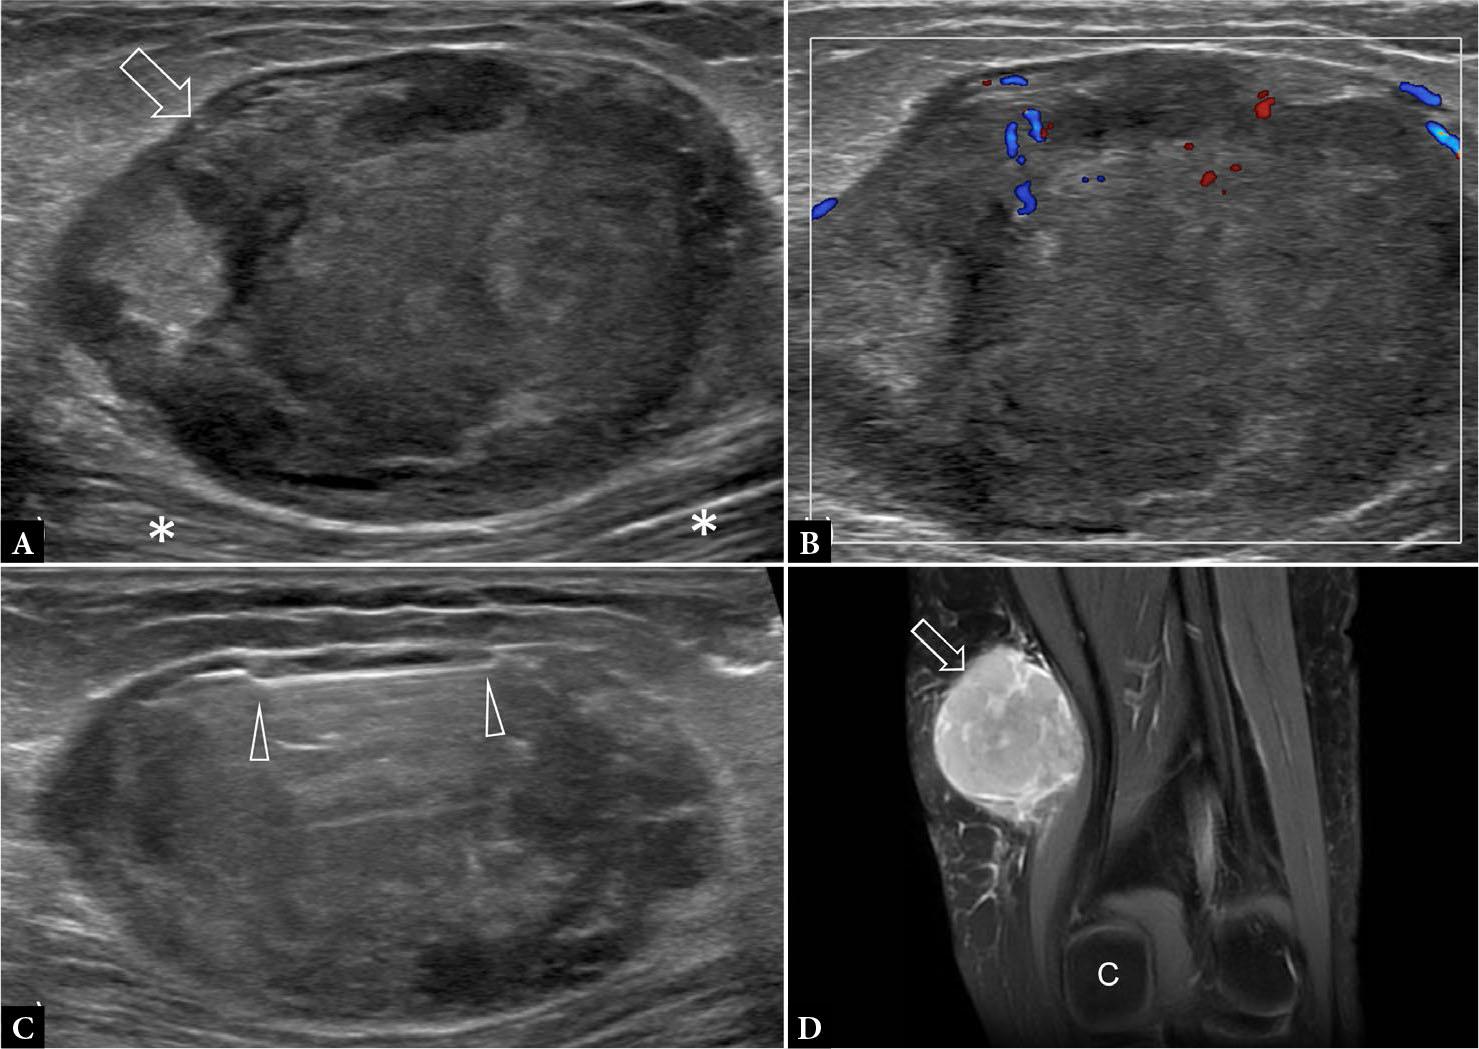

Fig. 7.

47-year-old female with slow-growing distal thigh mass for two years. Longitudinal A. greyscale and B. color Doppler US show a large well-encapsulated mildly hyperemic tumor (arrow) located between the investing fascia and the sartorius muscle (*). The overall appearance favored sarcoma. C. US image obtained during percutaneous biopsy shows sampling from the immediate subcapsular area of tumor (arrowheads). Histology was compatible with synovial sarcoma. D. T2-weighted fat-suppressed coronal MR image shows tumor (arrow) located proximal to medial femoral condyle (C) displacing the sartorius muscle deeply. Wide excision was performed with a 2 mm rim of muscle. No muscle invasion was present